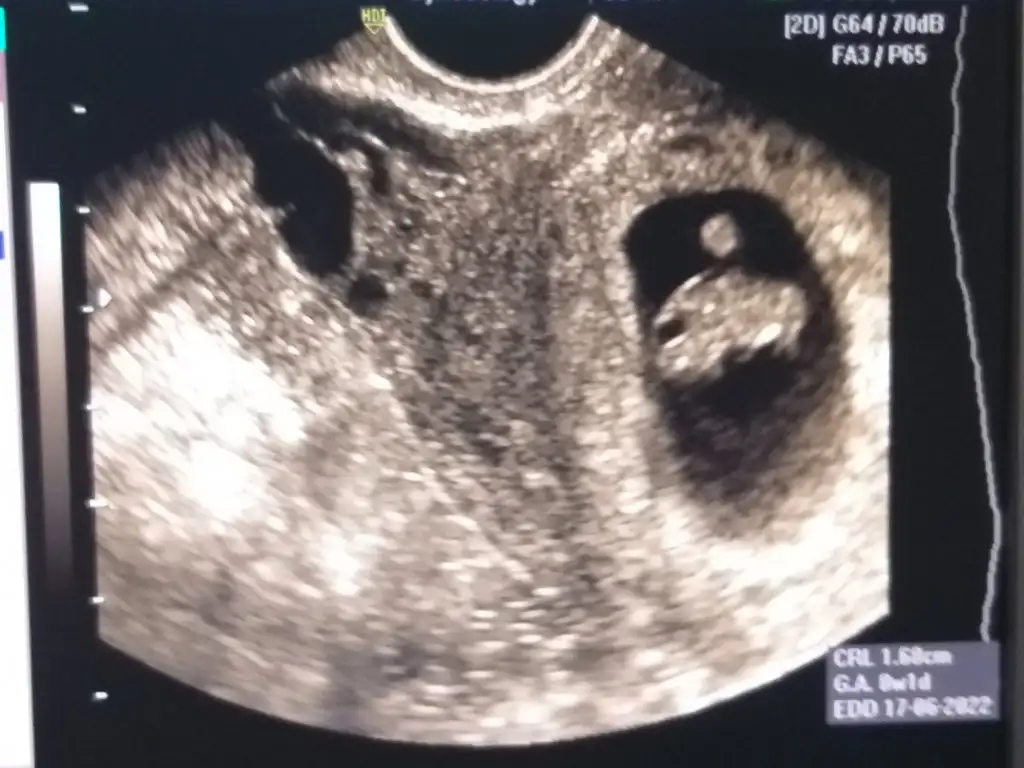

Kızçelerimm geldim geldimm iyi haberlerle çok şükür🙏🏻🙏🏻 Bebişimm çokk iyi tekme atıyordu sıpaa 😍 ama plasenta tam rahim ağzında olduğu için kanamam olmuş yarın akşam proluton iğne yaptırcam boll istirahat edicem hiçç bir sorunnyok çok şükürr 🙏🏻🙏🏻 O kadar rahatladım ki 🙏🏻 Gittiğimde yatış operasyon vs olur diye önce covid testi daha sonra damar yolu vs açtılar vallahi çok endişelenmiştim bi oh çektim şimdi🙏🏻🙏🏻❤️❤️